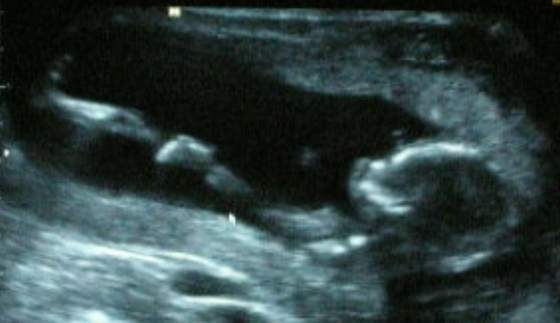

Cieszę się bardzo. Cudne te zdjęcia